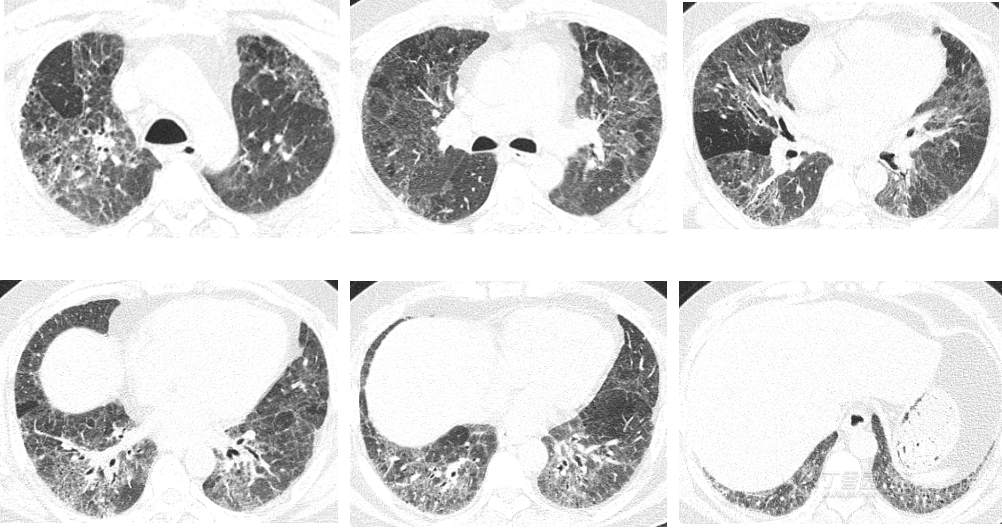

CT---肺窗